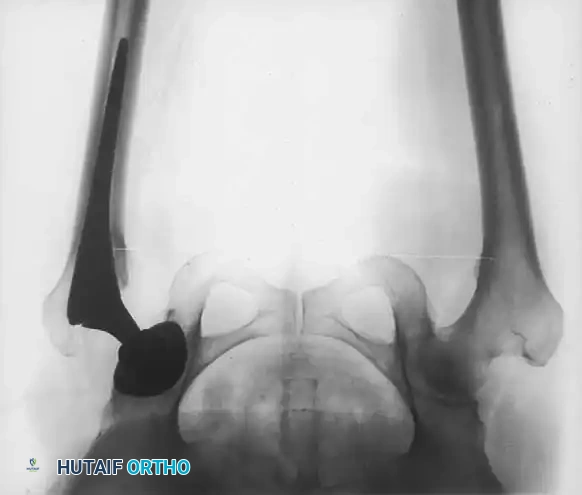

Standard preoperative radiographs must include an anteroposterior (AP) view of the pelvis centered over the pubic symphysis (with the hips internally rotated 15 degrees to profile the femoral neck) and a lateral view of the affected hip.

1. Determine Leg Length Discrepancy: A horizontal reference line is drawn across the bottom of the radiographic teardrops or the ischial tuberosities. The difference in the perpendicular distance from this line to a reproducible landmark on the proximal femur (usually the lesser trochanter) approximates the amount of limb shortening.

2. Acetabular Templating: The acetabular template is positioned at a 40- to 45-degree angle of inclination. It should correspond closely to the subchondral bone plate, ensuring adequate lateral coverage and medialization to the true floor (ilioischial line). The new center of rotation is marked.

3. Femoral Templating: The femoral template that most closely matches the proximal and distal size and contour of the femoral metaphysis and diaphysis is selected.

4. Neck Length and Offset: The neck length and offset are estimated to restore the abductor moment arm. The anticipated level of the femoral neck resection is marked relative to the lesser trochanter.

Fig. 7-40 Templating of radiographs for preoperative planning. A, Line drawn across the bottom of the pelvis to assess limb shortening. B, Acetabular template placed to mark the new center of rotation. C, Femoral template matching the metaphysis. D, Neck length and offset estimation.